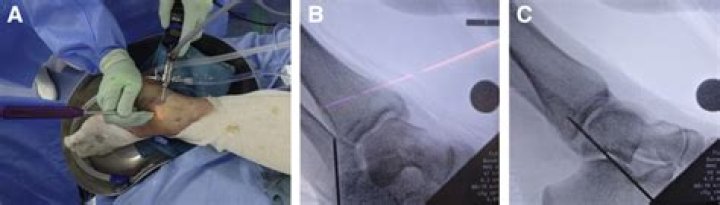

Our preferred treatment for peroneal tendon subluxation in athletes is to deepen the fibular groove, remove the low lying muscle belly (if necessary) and tighten the superior peroneal retinaculum.